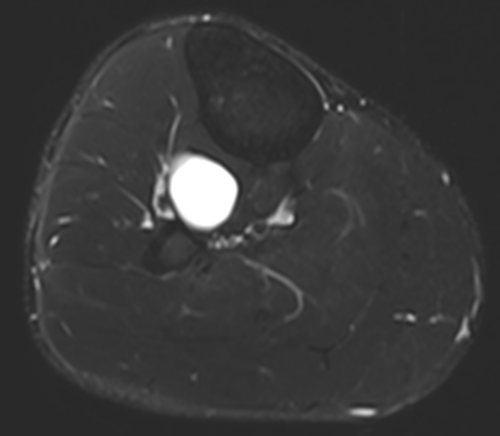

Ganglion cyst compressing deep common peroneal nerve